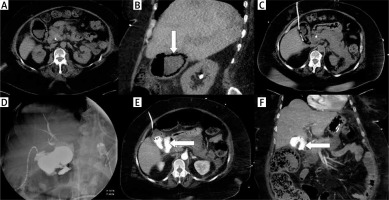

Photo 4

A case of fulminant septic status and cholecystostomy performed in emphysematous cholecystitis. Nonenhanced CT examination in transversal (A) and coronal plane (B) revealed a gallbladder wall containing gas (arrow). The drain was inserted using the transabdominal approach (C). Cholecysto-cholangiography through the drain was performed 7 days after the procedure and revealed discontinuity of the gallbladder wall (D). Computed tomography examination was performed immediately after cholangiography and confirmed the perforation in transversal (E) and coronal plane (F); leakage is noted with arrows